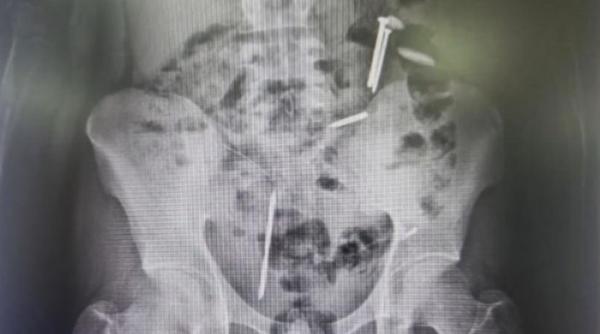

Nampak paku dan benda asing lainnya dalam hasil ronsen Mohamad Vemas Agung, remaja asal Jember (Foto: iNews TV)

JEMBER, iNewsSumba.id – Temuan benda asing berupa paku, koin, dan kawat di dalam tubuh remaja asal Jember, Mohamad Vemas Agung, menimbulkan perhatian publik. Kasus ini diduga berkaitan dengan perilaku mengonsumsi benda tak lazim yang sering dikaitkan dengan gangguan kesehatan mental.

Dalam pemeriksaan awal, petugas melakukan rontgen yang kemudian mengungkap adanya benda logam di dalam tubuh korban. “Saat dicek ronsen ditemukan benda asing dalam tubuhnya seperti dua buah paku, koin dan kawat,” jelasnya.